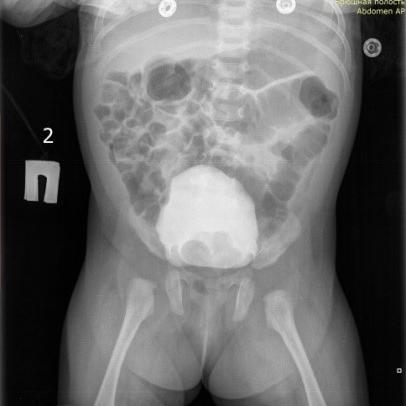

Данные инструментальных методов исследований:

УЗИ МВС:ЧЛС расширена: передне-задний размер лоханки 48 мм, продольный размер 62 мм, чашечки 10-22 мм, в просвете ЧЛС - моча со взвесью, паренхима различной толщины 4-8 мм

В дистальном отделе визуализируется два левых мочеточника: шириной 7 мм и 13 мм.

МОЧЕВОЙ ПУЗЫРЬ - содержит около 113 мл мочи со взвесью, контуры ровные, стенки не утолщены; после микции - содержит около 36 мл остаточной мочи.

КТ органов брюшной полости от 2025 Левая почка гидронефротически трансформирована, слой паренхимы истончен толщиной до 4-7 мм, члс деформирована, расширена: чашечки до 14 мм в поперечнике, лоханка шириной до 22,5 мм. Левый мочеточник имеет извитой ход, в средней трети расширен до 10 мм, в нижней трети, в области устья шириной до 12 мм. В отсроченную фазу (15 мин)- слева определяется 2 лоханки, дистальнее прослеживается единственный мочеточник. В левом мочеточнике контраст не визуализируется.